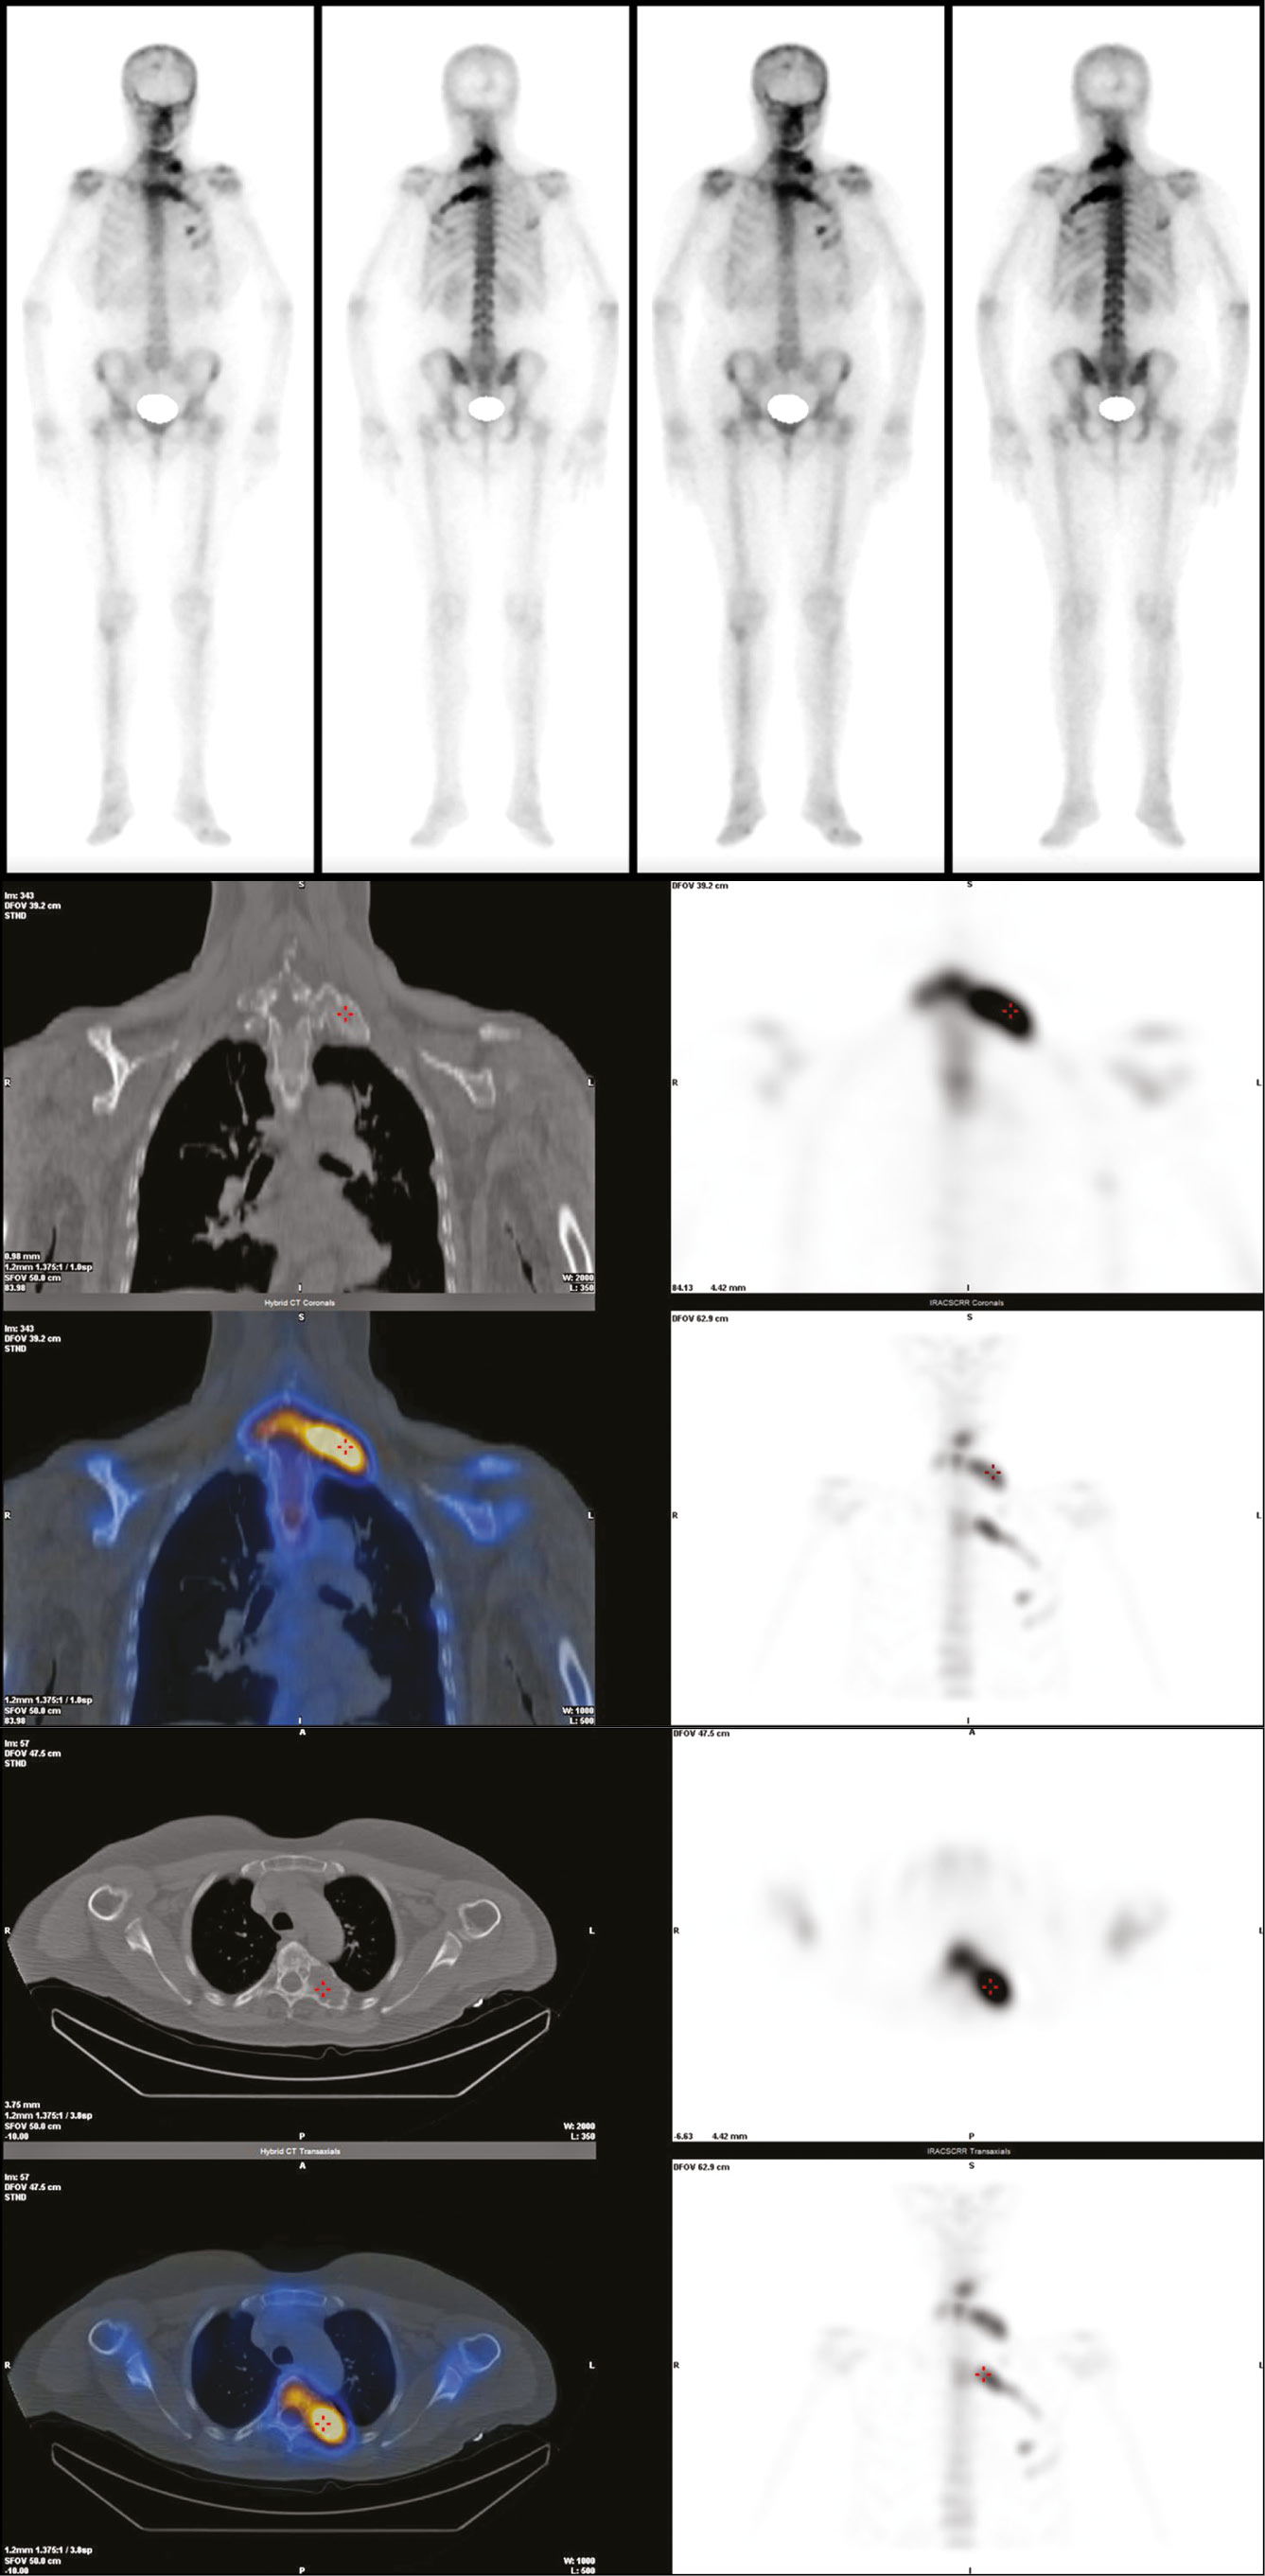

The whole body Fluorine-18 Fluorodeoxyglucose PET-CT scan confirmed the involvement of each of the above-mentioned skeletal segments and identified with other imaging methods but, paying special attention to some of them that showed more intense uptake of the radiotracer, specifically the posterior arch of the first left rib, the fifth vertebral body, and the left posterior arch of the corresponding rib (Fig. 4).

Fig. 4. 18F-FDG PET-CT scan showing an increased tracer uptake at the posterior arch of the first left rib (4a), the fifth dorsal vertebra, and the posterior arch of the corresponding left rib (4b).

Additionally, the presence of a marked metabolic activity at these levels was confirmed by the SPECT-CT scan, which showed two areas of intense and pathological focal accumulation of the osteotropic tracer (99mTc-HDP) in the left paravertebral side. The upper one, corresponds to the first dorsal vertebra, with an SUV max of 39.91, and the other at D5-fifth left rib with an SUV max of 47.06 (Fig. 5).

Fig. 5. The whole body SPECT-CT confirmed the involvement of the above-mentioned bone segments and no other particularly shows two areas of high pathological focal accumulation of the osteotropic tracer (99mTc-HDP) in the left paravertebral side (D1 and D5-fifth left rib).